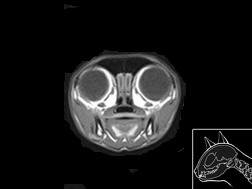

Atlas cérébral du chat IRMT2

IRM T2

31 coupes

Atlas cérébral du chat IRMT1

IRM T1

>> 31 coupes